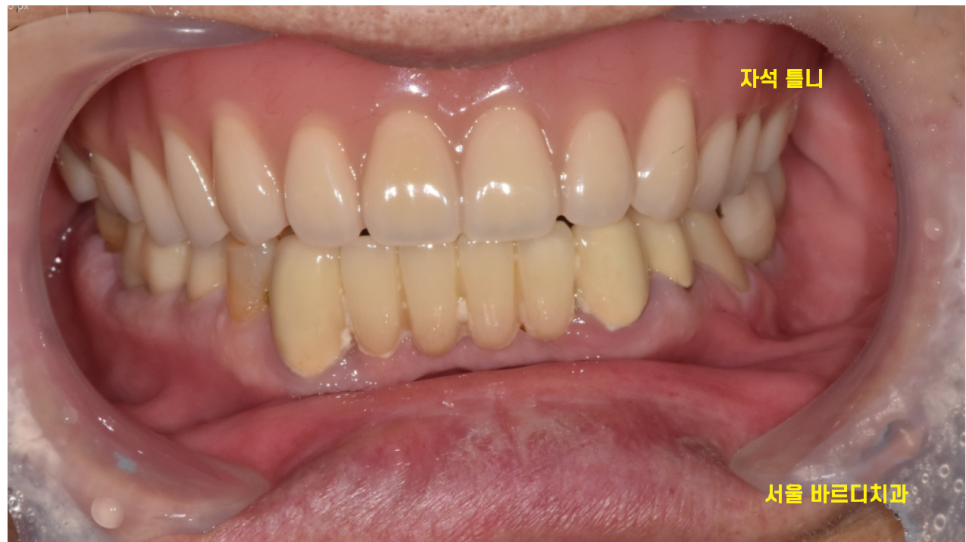

240411

겉으로 보았을 때는

일반 틀니와 똑같지만..?

240228

엑스레이를 찍어보면

임플란트가 심어져 있답니다.

임플란트와 틀니를 자석으로 연결하니

접착력이 좋다

잘 안떨어진다~~~